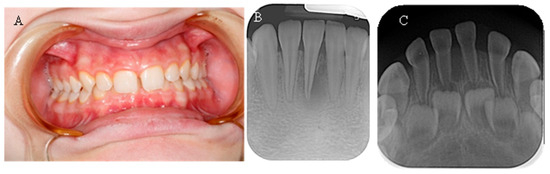

No taurodontism was detected when comparing the panoramic X-rays of hypophosphatemic children with those of healthy patients. In most of them, a normal thickness of the root dentin was observed. When comparing a periapical radiograph of the upper anterior region of a child with a primary dentition and hypophosphatemia due to a central incisor trauma with a similar X-ray of a healthy child of the same age, significantly wider pulp chambers and a thin layer of coronal and root dentin were noted (Figure 3). This symptom was observed in 27.27% of the children examined in this study.

Figure 3. (A) OPG of a 15-year-old girl with XLH; (B) OPG of a healthy 15-year-old girl; (C) Periapical X-ray of a 3-year-old boy with XLH; (D) Periapical X-ray of a 3-year-old healthy boy.